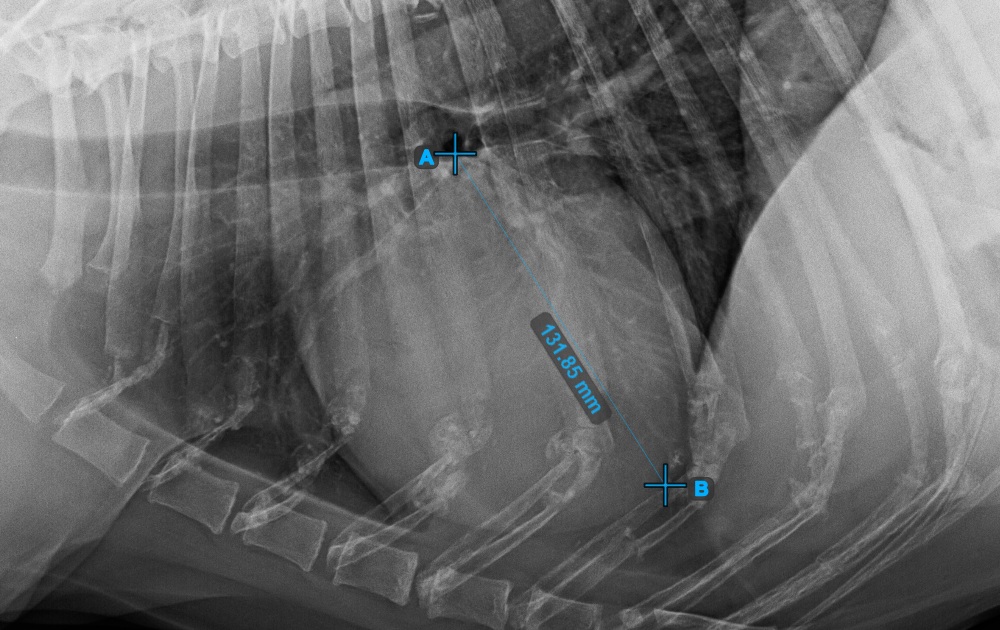

Vervollständigen Sie die Längsachse des Herzens, indem Sie den Apex-Punkt in der Nähe der Herzunterseite markieren.

Das Bild unten zeigt die typische Platzierung des Apex-Punkts.